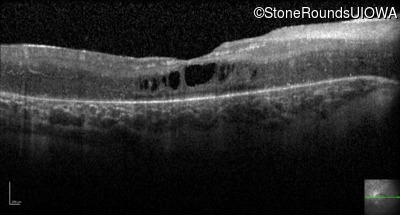

Optical Coherence Tomography - Right - 20/200 -2

Exemplar / OCT Stack

OCT Stack